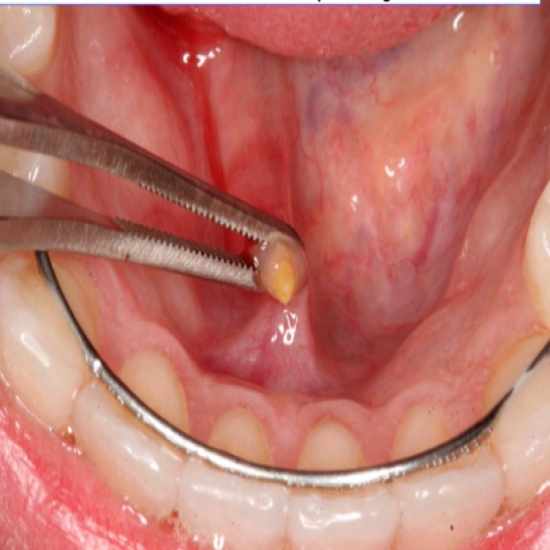

أورام الغدد اللعابية هي أنواع نادرة من الأورام التي تبدأ في الغدد اللعابية. علاج سرطان الغدة. في حالات نادرة فقط عندما تتواجد الحصوة عميق ا داخل الغد ة ولا يمكن استخراجها بطريقة داخلي ة عبر تجويف الفم يتم استخدام الطريقة الخارجي ة وبالتالي يجب استخراج الغد ة اللعابي ة بأكملها.

علاج الحصوة في الغدة اللعابية طب الأعشاب شاهدوا قناة الناس على تردد رأسي 12054 تابعوا قناة الناس عبر المواقع. حصوات الغدد اللعابية هي ظاهرة تسمى التحصي اللعابي sialolithiasis وتنجم عن انسداد في القنوات اللعابية. تتكون الحصوات اللعابية في قنوات الغدد اللعابية وتكون صلبة في الغالب وتسبب تورمات وآلاما في الفك وفي الوجه.